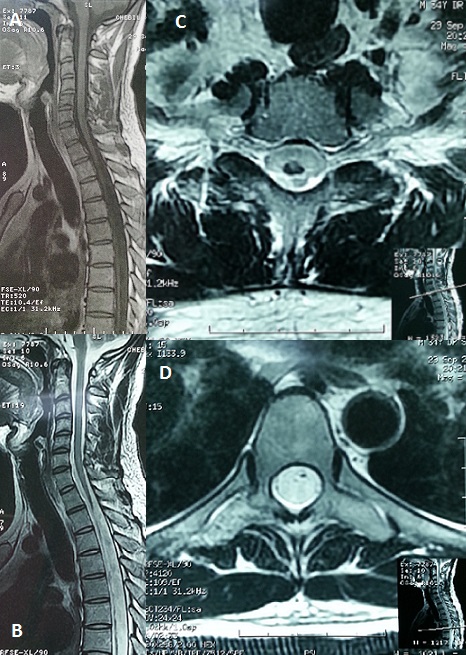

L'accident de décompression médullaire constitue la majorité des accidents de plongée (40 à 45%). Dans 20 à 30% des cas, les plongeurs conservent des séquelles neurologiques de gravité variable dont 10% de formes invalidantes. L'existence de signes déficitaires moteurs précoces, d'une aggravation des symptômes pendant le transport vers le centre hyperbare, et l'apparition de troubles sphinctériens sont des facteurs de mauvais pronostic. La symptomatologie des accidents de décompression médullaire est en rapport avec la survenue d'une ischémie aigue de la moelle épinière dont l'origine est imparfaitement comprise. Nous rapportons le cas d'un patient âgé de 34 ans, sans antécédents, plongeur professionnel, qui a présenté suite à un accident de plongée à 110 m, puis une remontée rapide une détresse respiratoire et une lourdeur des deux membres inférieurs. Il a été transporté dans un caisson hyperbare à l'hôpital. L'angioscanner réalisé en urgence a mis en évidence une embolie pulmonaire segmentaire antéro-basale droite. L'IRM cérébromédullaire a montré une lésion en hyper signal étendue de C3 à C6 d'allure ischémique. Après un an d'évolution, le patient garde toujours une paraplégie complète flasque ASIA A niveau D4 avec une anesthésie tactile et thermo-algésique, des réflexes ostéo-tendineux abolis, une hypotonie anale, des escarres (sacrée, trochantérienne gauche, ischiatique droite) stade III et une amyotrophie des deux membres inférieurs. Une IRM médullaire réalisée a montré une atrophie médullaire très importante étendue de D2 jusqu'au cône terminal (A, B, C, D). L'évolution d'un accident de plongée est imprévisible, avec un risque non négligeable de séquelles neurologiques.